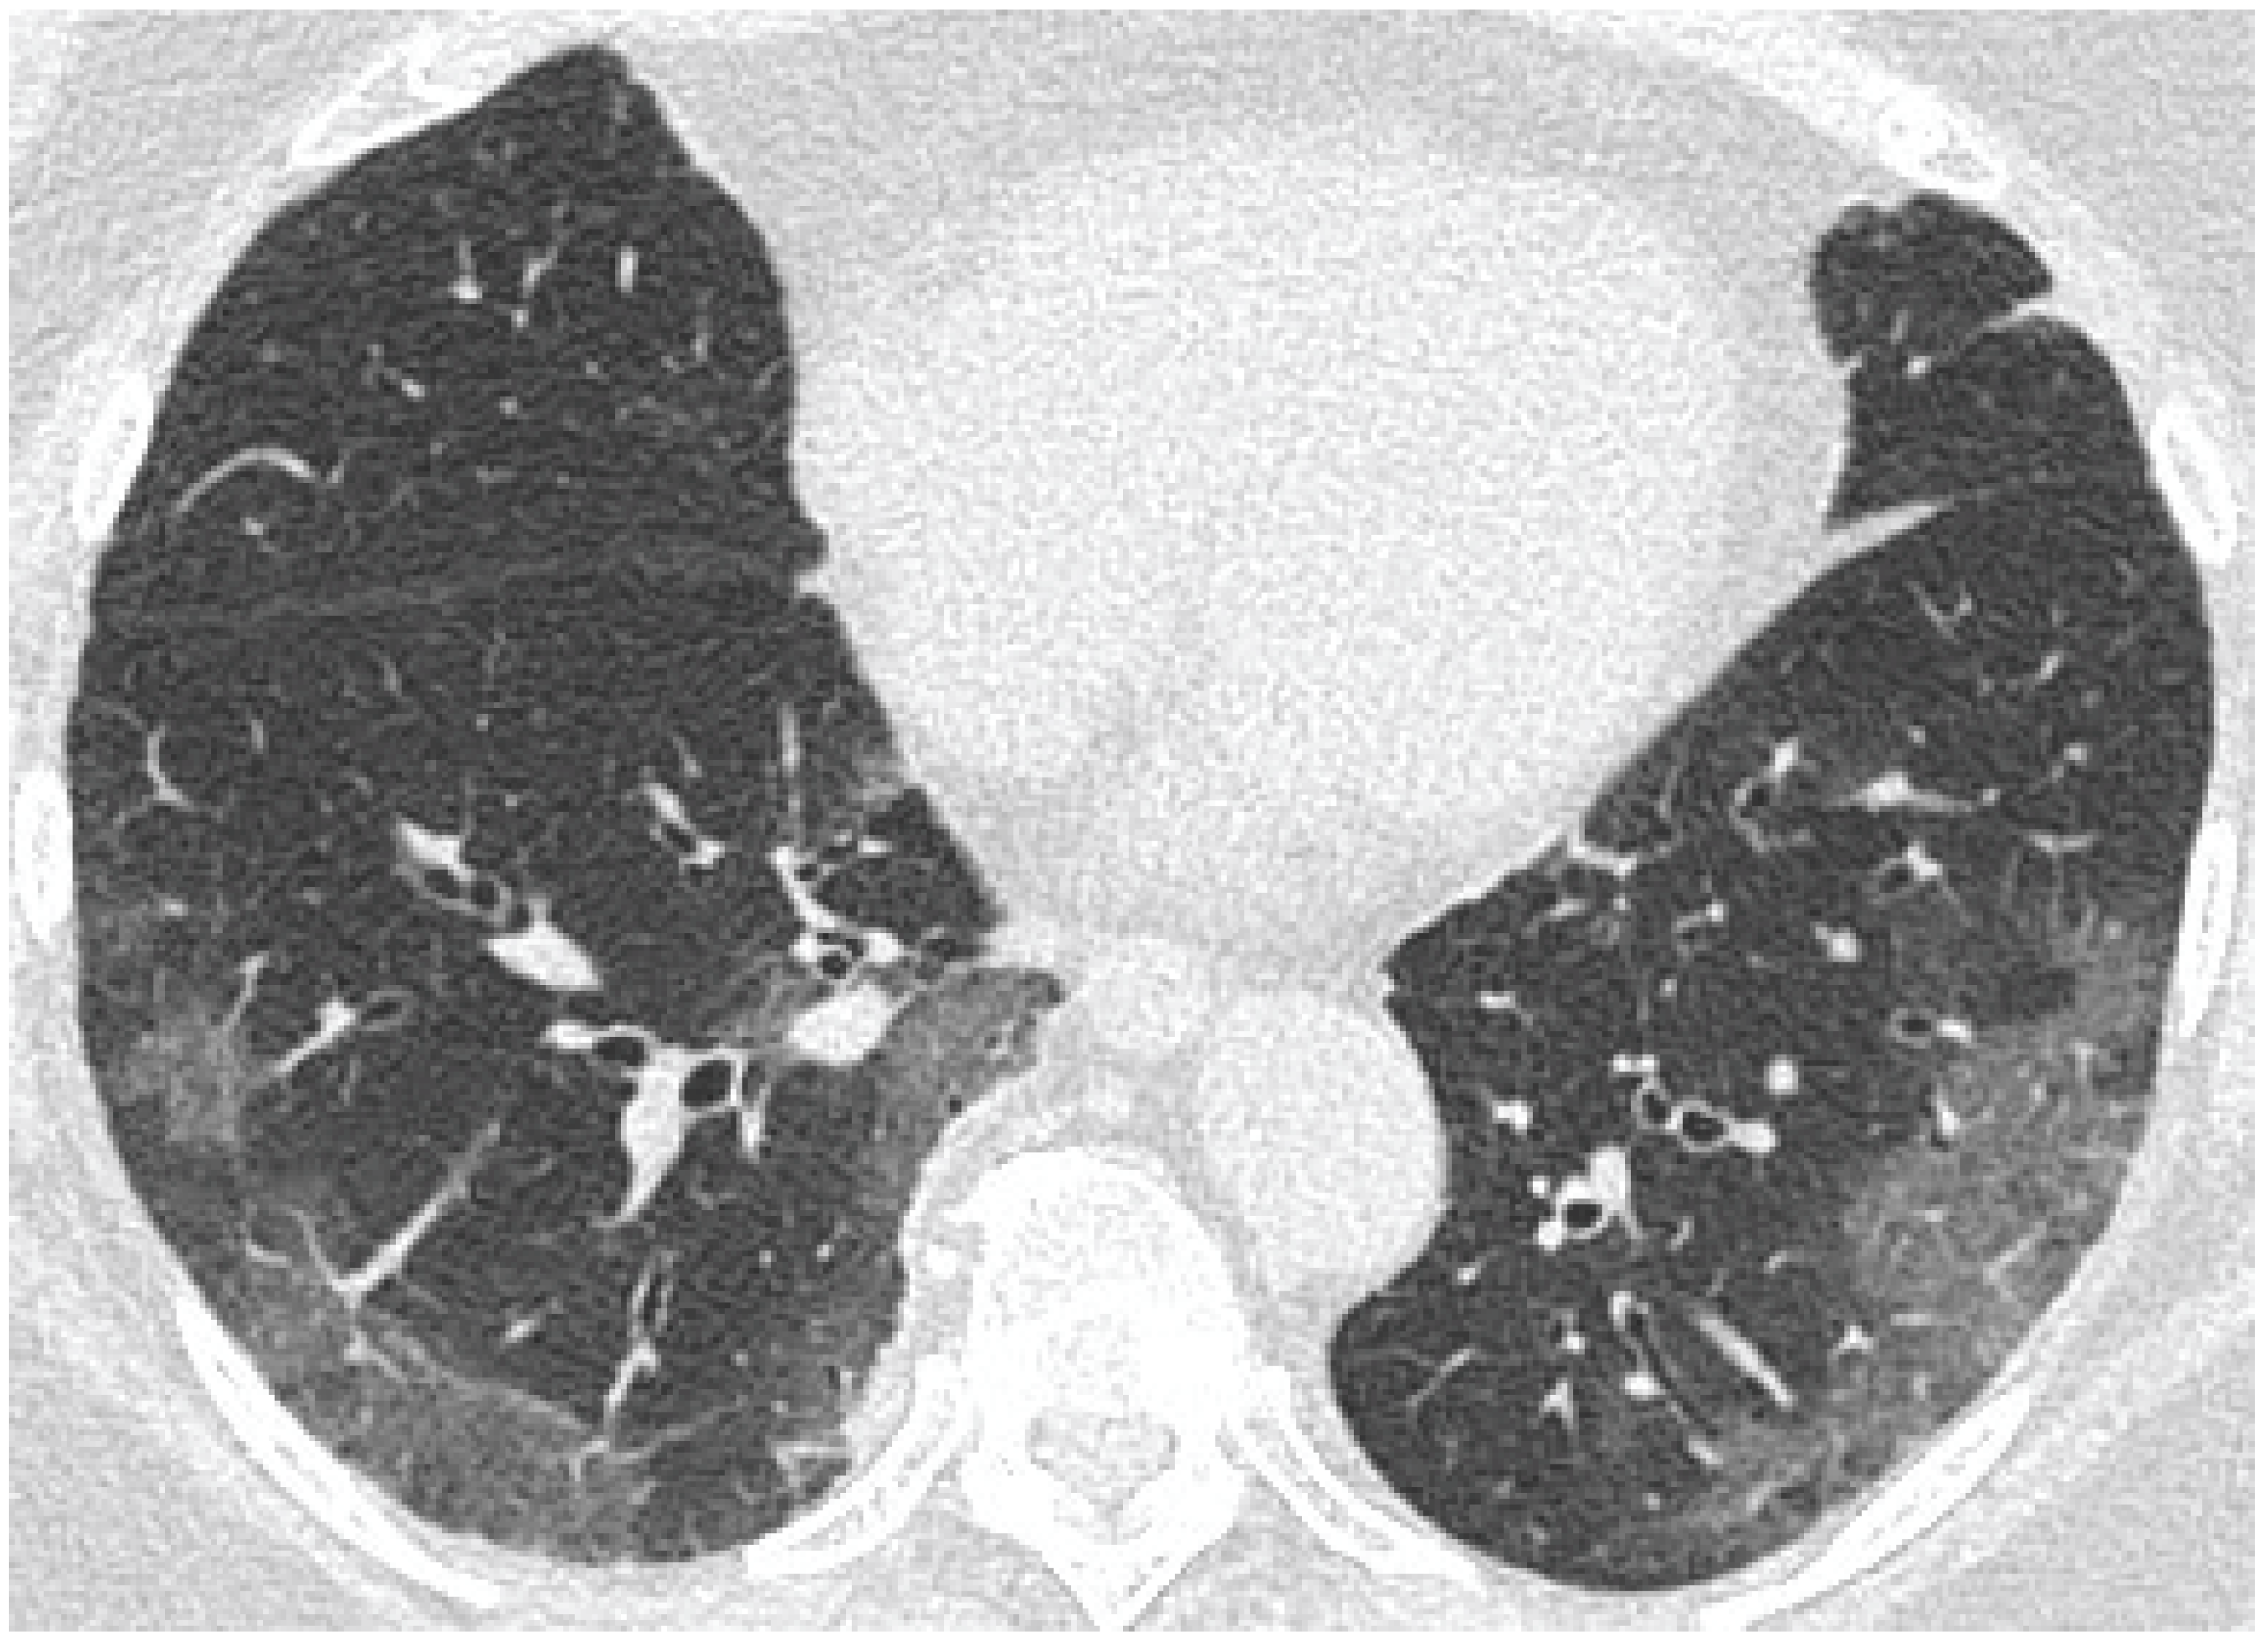

- GGO was defined as hazy increased attenuation of lung with preserved bronchial and vascular margins;

- Consolidation was considered an increase in pulmonary parenchymal attenuation that obscures the airways and vessels;

- Crazy paving was the area of GGO with coexisting thickening of interlobular septae;